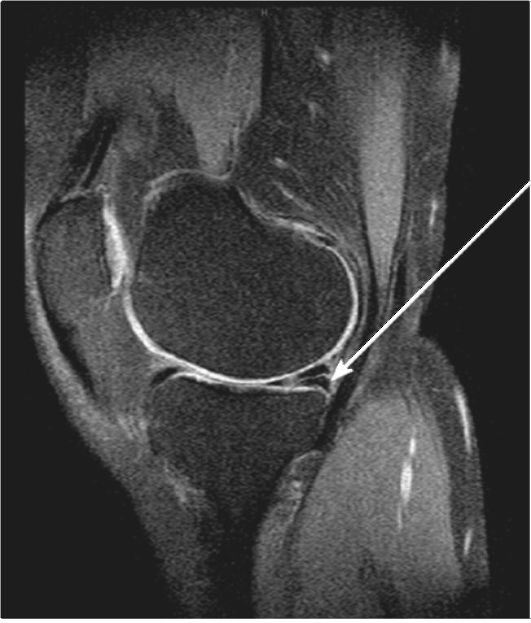

МРТ является информативным методом скрытых (рентгенонегативных) переломов костей, не видимых на рентгенограммах. Кроме

того, этот метод незаменим при выявлении травм связок, менисков (рис. 3-13) и суставного хряща.

Рис. 3-13. МРТ коленного сустава. Разрыв заднего рога медиального мениска